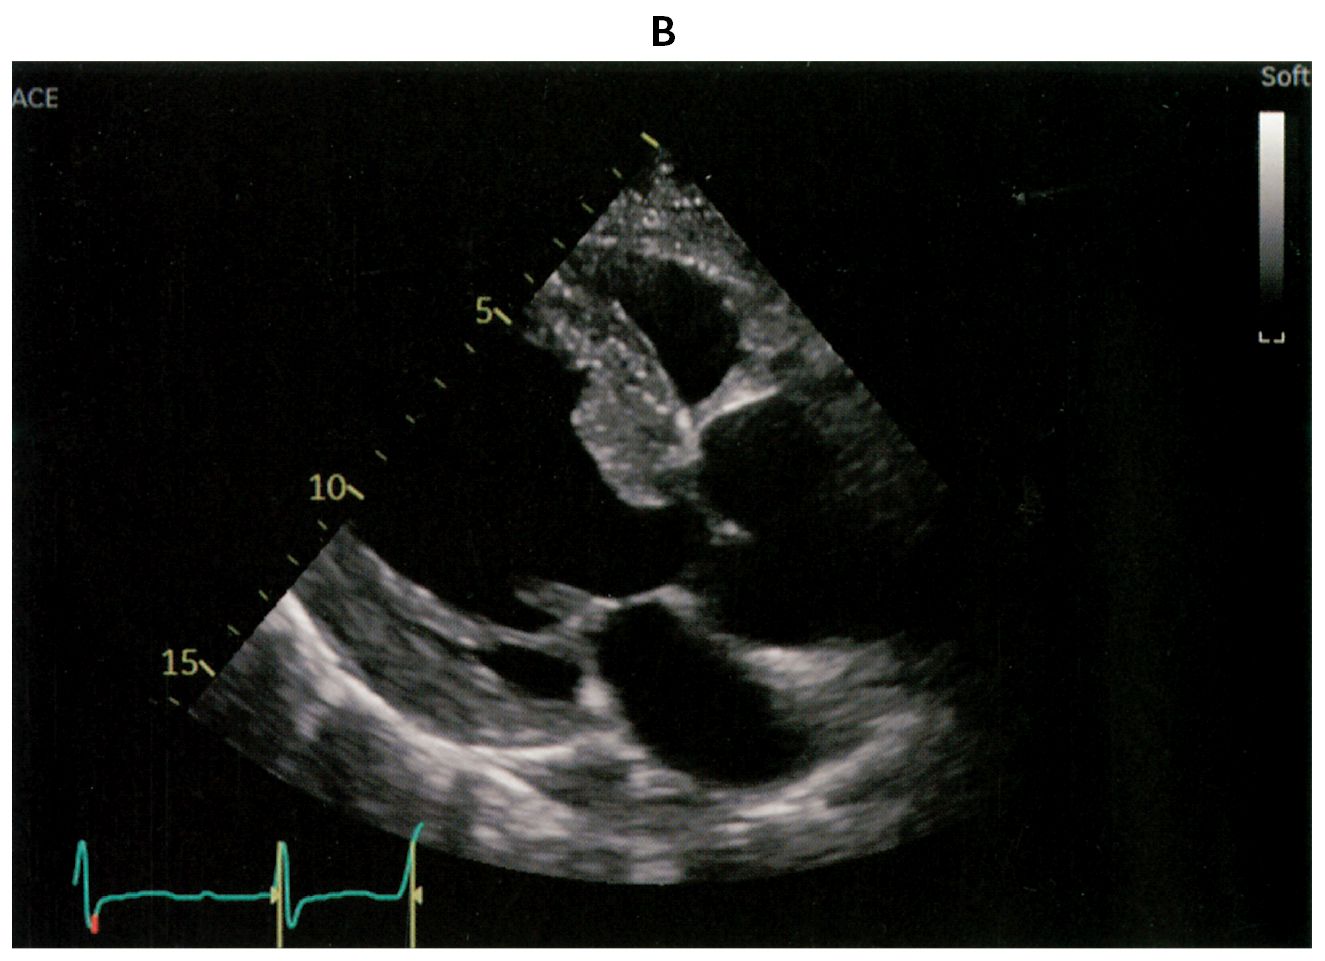

76歳の男性。定期受診で来院した。3年前に拡張期心雑音を指摘され,定期的に心エコー検査で経過観察をしてきた。今回,6か月ぶりの心エコー検査と定期外来で受診し,労作時の息切れを認めた。意識は清明。身長168cm,体重72kg。体温35.8℃。脈拍72/分,整。血圧142/46mmHg。SpO2 98%(room air)。頸静脈の怒張を認めず,呼吸音に異常を認めない。胸骨左縁第3~4肋間にLevine 2/6の拡張期雑音を認める。腹部は平坦,軟で,肝・脾を触知しない。四肢に浮腫を認めない。血液生化学所見:尿素窒素14mg/dL,クレアチニン0.8mg/dL,血糖106mg/dL,HbA1c 6.4%(基準4.9~6.0),BNP 245pg/mL(基準18.4以下)。胸部エックス線写真(A)を示す。心電図では,V4~V6胸部誘導で高電位を認める。心エコー図(B)とカラードプラ心エコー図(C)とを下に示す。心エコー検査では,左室拡張期径69mm,左室駆出率46%,大動脈弁輪の拡大と重症の大動脈弁閉鎖不全症を認める。胸部造影CTでも,著明な大動脈弁基部の拡張を認める。冠動脈造影検査で冠動脈に病変を認めなかった。